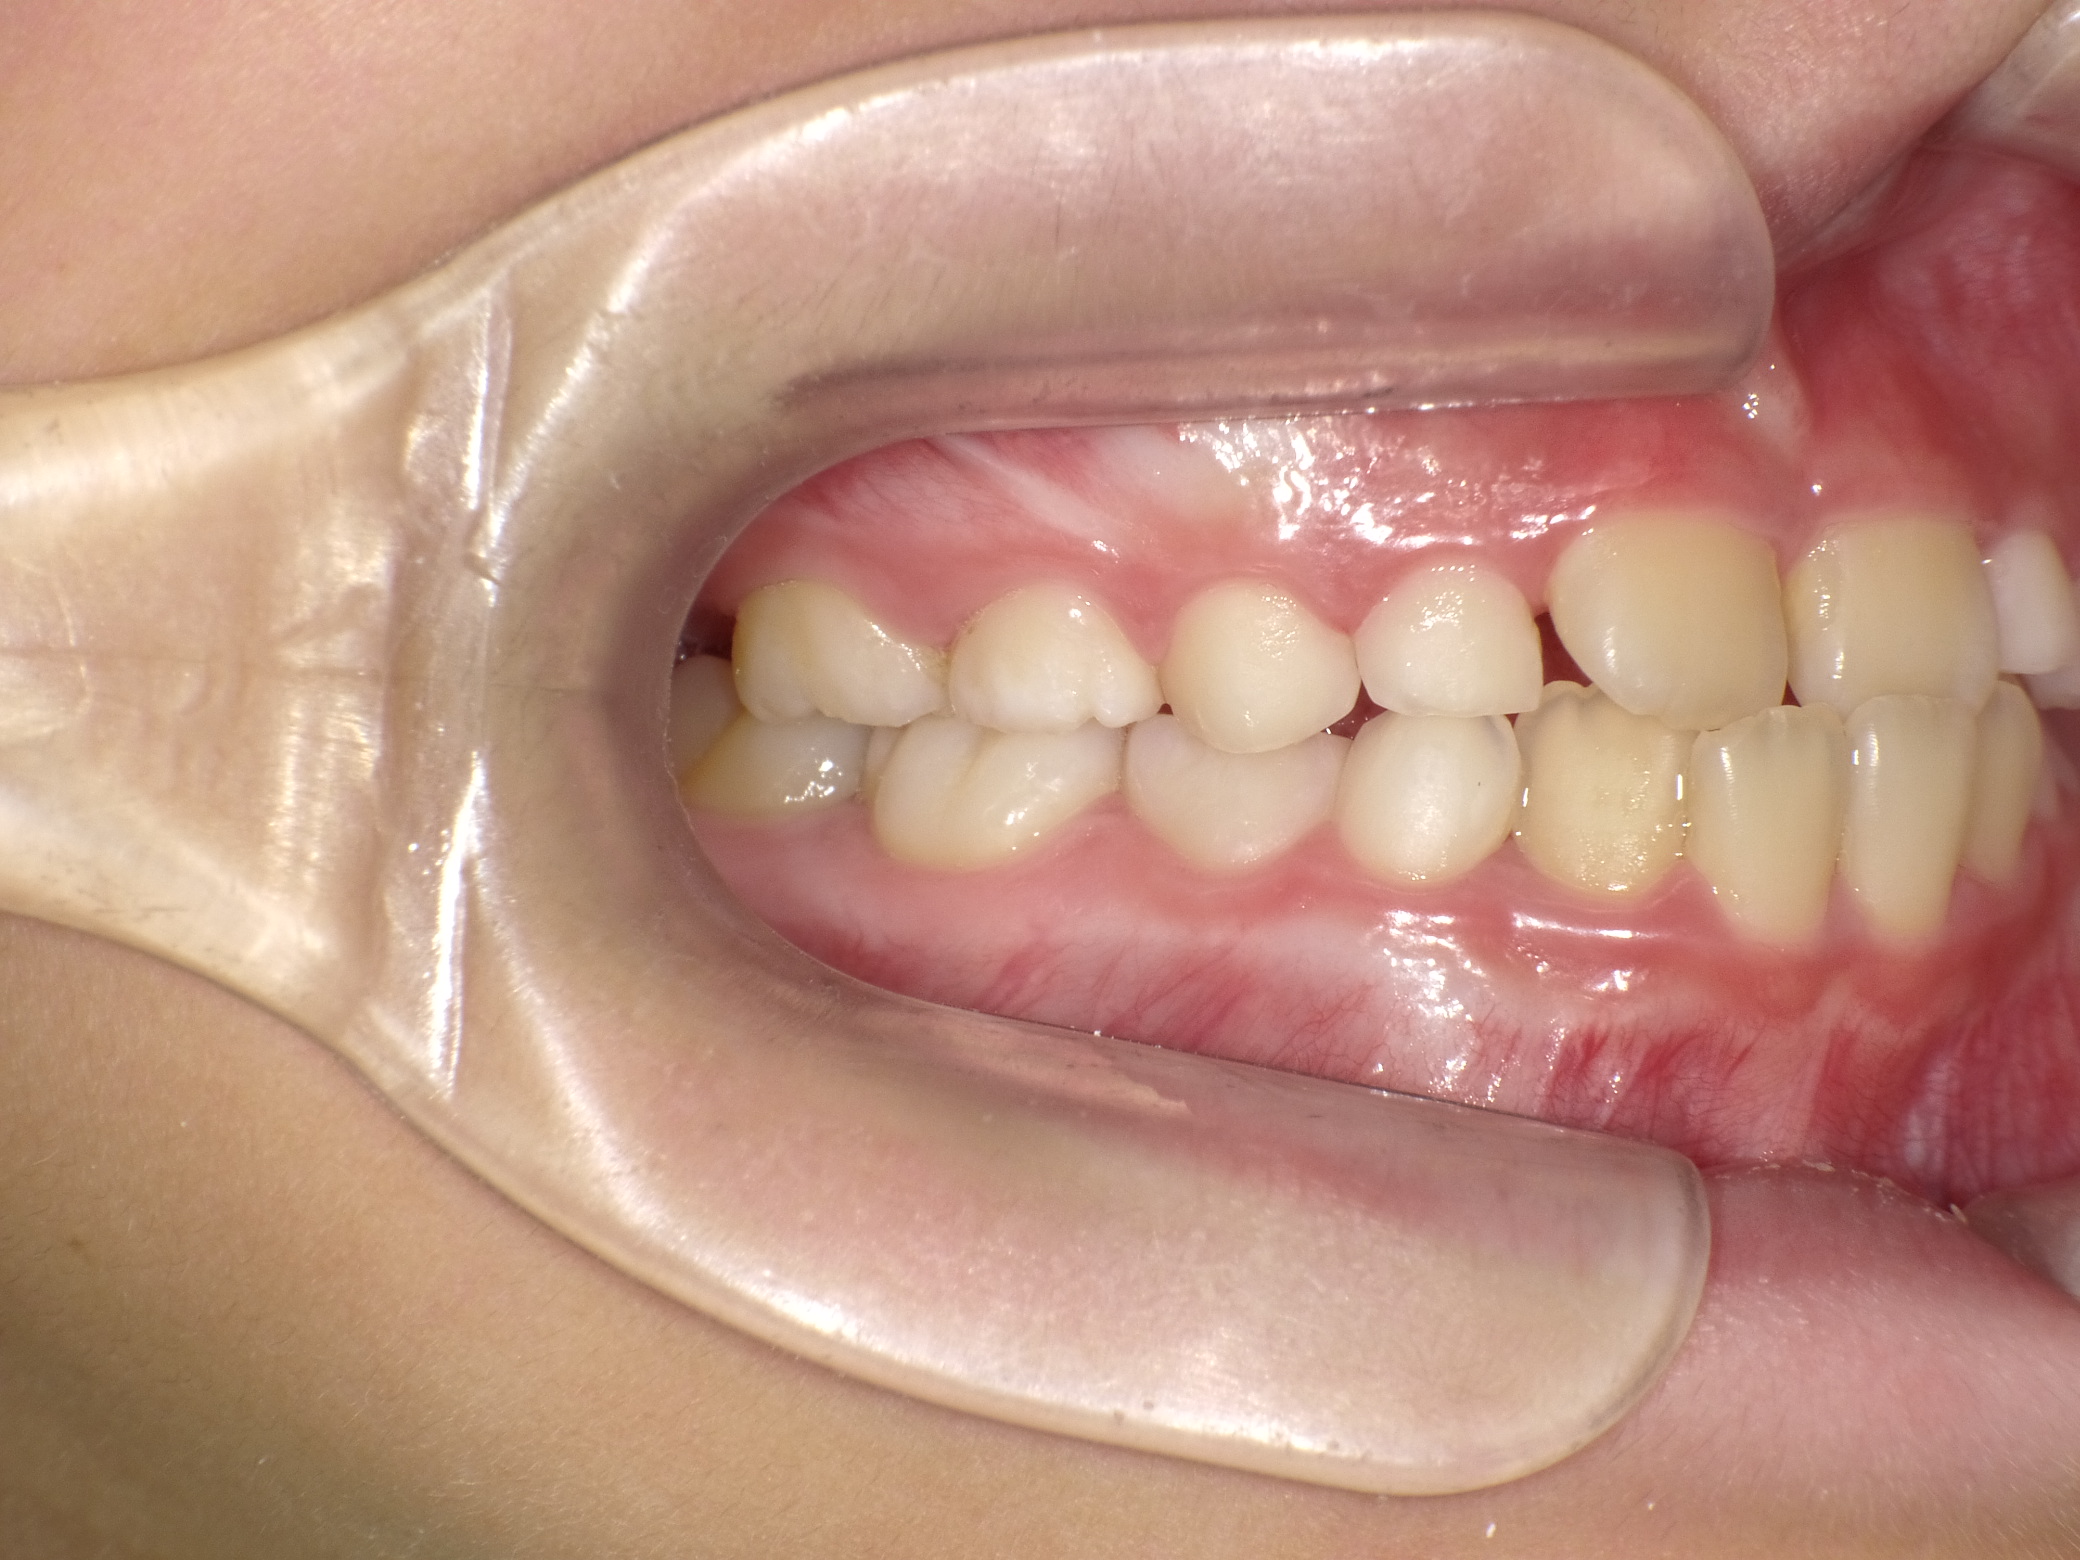

【小学生】マイオブレース矯正 反対咬合を改善

小学生で開始

マイオブレース

受け口

非抜歯

1期治療のみで改善

Before

After

治療期間

1.6年

治療開始

8歳

種類

マイオブレース矯正

使用装置

機能矯正装置

コメント

治療にしっかり取り組んでくれたのでスムーズに治りました。

治療後3年経過した今でも 装置もいれずに 後戻りもしていません。